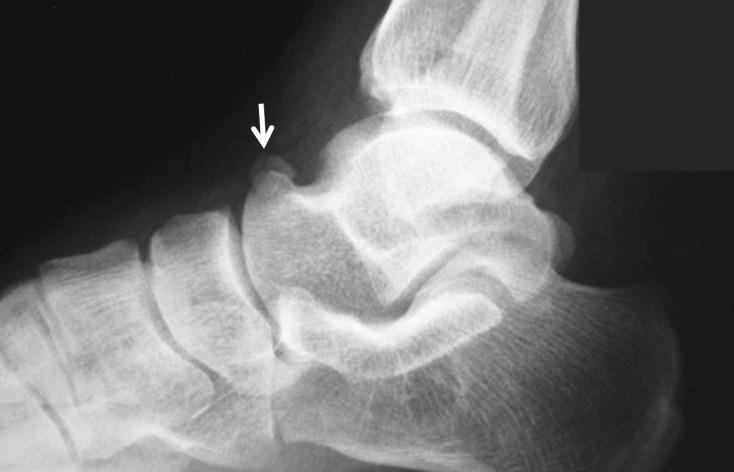

Accessory ossicles of the foot and ankle are normal variants of bone development that usually remain asymptomatic. However, they may be involved in various disorders and become a source of pain such as in fractures, dislocations, degenerative changes, osteonecrosis, osteoarthritis, osteochondral lesions, avascular necrosis, and irritation or impingement of adjacent soft tissues. Hence, during the assessment of the situations above, knowledge about these little-known ossicles could be very important to reach the correct diagnosis. Recent studies in the literature have mostly focused on the most frequent 9-12 accessory bones. In this review, 24 types of accessory ossicle are described. These ossicles are accessory navicular bone, os peroneum, os trigonum, os intermetatarseum, os vesalianum. os subfibulare, os subtibiale, os calcaneus secundarius, os calcanei accessorium, os supratalare, os sustentaculi, os talotibiale, os tali accessorium, talus secundarius, os subcalcis, os cuboideum secundarium, os supranaviculare, os infranaviculare, os paracuneiforme, os intercuneiforme, os cuneometatarsale I tibiale, os cuneometatarsale plantare, os cuneo-I metatarsale-II dorsale, and os aponeurosis plantaris. The clinical importance of these bones should be known thoroughly to reduce unnecessary orthopedic consultations and misdiagnosis. This article describes the clinical importance of the accessory ossicles and their possible pathological conditions. Understanding the possible disorders of the accessory ossicles of the foot and ankle can provide a more accurate diagnostic process.

足踝部的副骨是骨骼发育的正常变异,通常无症状。然而,它们可能参与各种疾病,并成为疼痛的来源,如骨折、脱位、退行性改变、骨坏死、骨关节炎、骨软骨损伤、缺血性坏死以及对相邻软组织的刺激或撞击。因此,在评估上述情况时,了解这些鲜为人知的小骨对于做出正确诊断可能非常重要。文献中的近期研究大多集中在最常见的9 - 12块副骨上。在这篇综述中,描述了24种副骨。这些副骨包括副舟骨、腓籽骨、三角骨、跖间骨、维萨里骨、腓下骨、胫下骨、跟骨副骨、跟骨副骨、距上骨、载距突、距胫骨、距骨副骨、第二距骨、跟下骨、第二骰骨、舟上骨、舟下骨、副楔骨、楔间骨、第一楔跖胫侧骨、楔跖足底骨、第一楔跖第二背侧骨和跖腱膜骨。应充分了解这些骨骼的临床重要性,以减少不必要的骨科会诊和误诊。本文描述了副骨的临床重要性及其可能的病理情况。了解足踝部副骨可能出现的疾病有助于提供更准确的诊断过程。